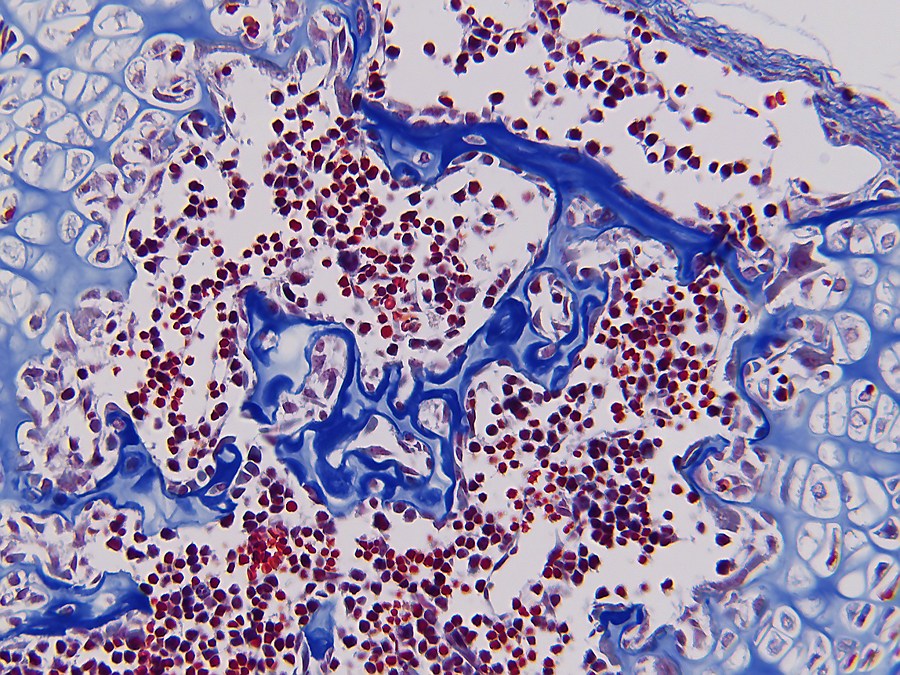

Bone formation or ossification[2] visualized by various histological stains.

In both cases, primary (braided or plexiform) bone is first formed, which is soon replaced by secondary (lamellar) bone, which may have a compact or spongy appearance macroscopically. During bone growth, areas of primary bone, bone breakdown, and secondary bone continually occur side by side. This coexistence of breakdown and creation (remodeling) continues in the adult body, although at a much slower rate.

Bone is composed of cells and intercellular material that is calcified, the bone or bone matrix. Three types of cells can be distinguished:

1. Osteoblasts (bone forming cells), which produce the organic components of the bone matrix. Osteoblasts arise from osteoprogenitor cells, which are found in endosteum[2] and periosteum[2]. Osteoblasts synthesize the organic components of the bone matrix and thus produce collagen type I, proteoglycans[2] and glycoproteins[2]. Osteoblasts are located in contiguous rows, the osteoblast hemisphere, against the surface of the bone;

2. Osteocytes (mature bone cells) formed by maturation of osteoblasts lie in cavities (lacunae) of the bone matrix. From these cavities, canaliculi run through the bone in different directions, containing the outgrowths of osteocytes. They make contact with each other through gap junctions[2], allowing the exchange of ions and small molecules;

3. Osteoclasts (bone-degrading cells); these are large multinucleated (up to fifty nuclei) cells that can break down bone. Osteoclasts are freely motile cells and lie as elongated cells against the bone margin, sometimes in a hollow created by them eating away matrix: the lacuna of Howship.

To observe the staining of bone forming tissue and the differences in staining, it was chosen to cut sections of similar tissue which was fixed in the same way. For this purpose, five-day-old mice were fixed in Bouin liquid. To allow the fixative to penetrate the tissue more easily, the extremities were removed and small incisions were made in the skin. Tissue was left in Bouin for approximately two months after which dehydration was started in ethanol 70%. The usual rinsing out of the fixative in water did not take place to prevent tissue from swelling too much[3]. Further ethanol steps were 85%, 95% and 100% with a duration of 48 hours per step. Via xylene, the switch to paraplast plus was then made. To ensure that all xylene was replaced with paraplast, three liquid paraplast baths were used.

- According to Masson-Goldner[4].

Dyeing protocols are mentioned below and are taken from 'Romeis Mikroskopische Technik' see Source Notes. The preparation of the dyes was carried out as described in Romeis but the staining times were adjusted empirically[2] for best results. Also dehydration after staining was often performed with isopropanol instead of ethanol 100% due to the high cost of absolute alcohol. After drying of the resin, images of the sections were taken with a Moticam 2300 digital microscope camera mounted on a Leitz Orthoplan microscope.